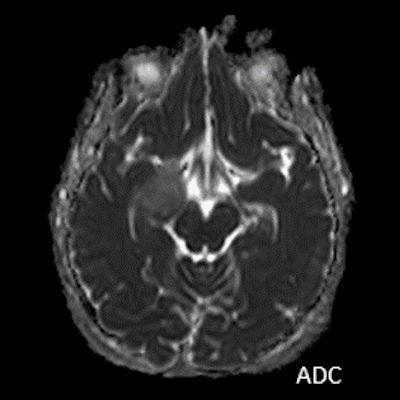

- B) Lezyon difüzyon görüntüde izo-hiperintens, ADC haritalamada hafif hiperintens izlenmiş olup (oklar) diffüzyon kısıtlılığı göstermemektedir. Lezyonun anterior kesiminde kontrastlı serilerde yamalı kontrast tutulumları (oklar) mevcuttur. MR spektroskopide lezyon düzeyinden elde olunan multivoksel görüntülerde kolin pikinde artış ve NAA da azalma (oklar) dikkati çekmektedir. Kolin/kreatinin oranı 1.76 olarak ölçülmüştür.